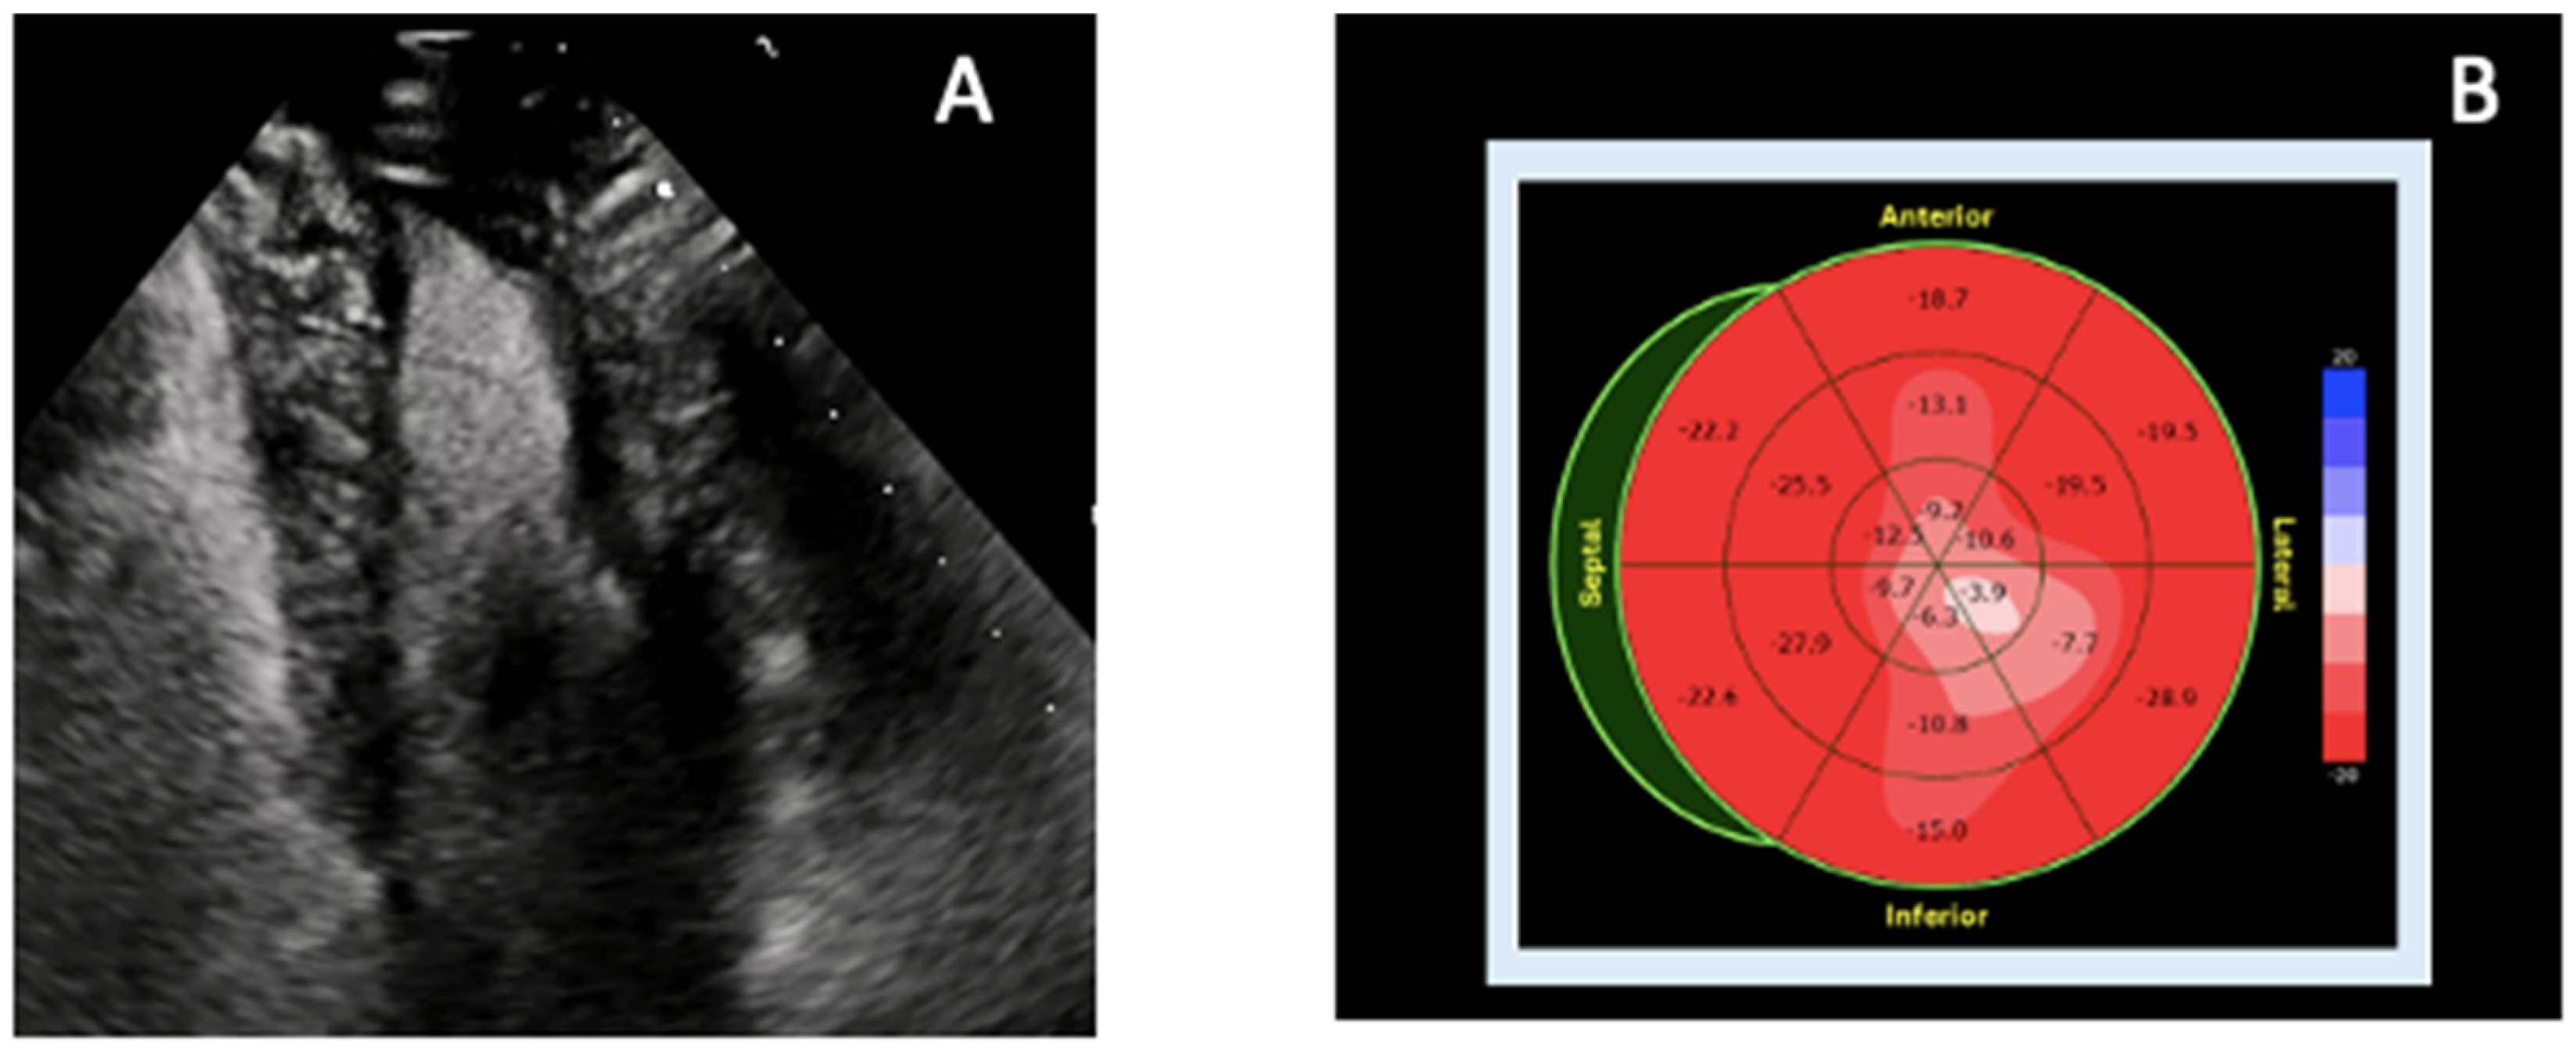

4.2. Apical Hypertrophic Cardiomyopathy

| Apical HCM | Apical wall thickness ≥15 mm; systolic cavity obliteration; apical aneurysm possible | Preserved or mildly reduced apical strain; increased basal strain | Focal apical hypertrophy; patchy LGE; normal/mildly ↑ T1 | CT useful if poor echo window |